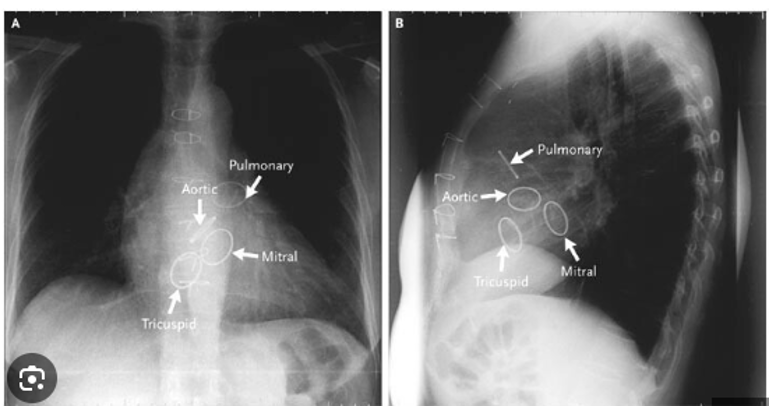

Q

CXR showing valve replacement , which one is it? (there were two valves, it was pointing to the AV)

a) Aortic valve

b) Mitral valve

c) Pulmonary valve

d) Tricuspid valve

A

Also consider frequency gamble that Pulmonary and tricuspid valves are less commonly replaced